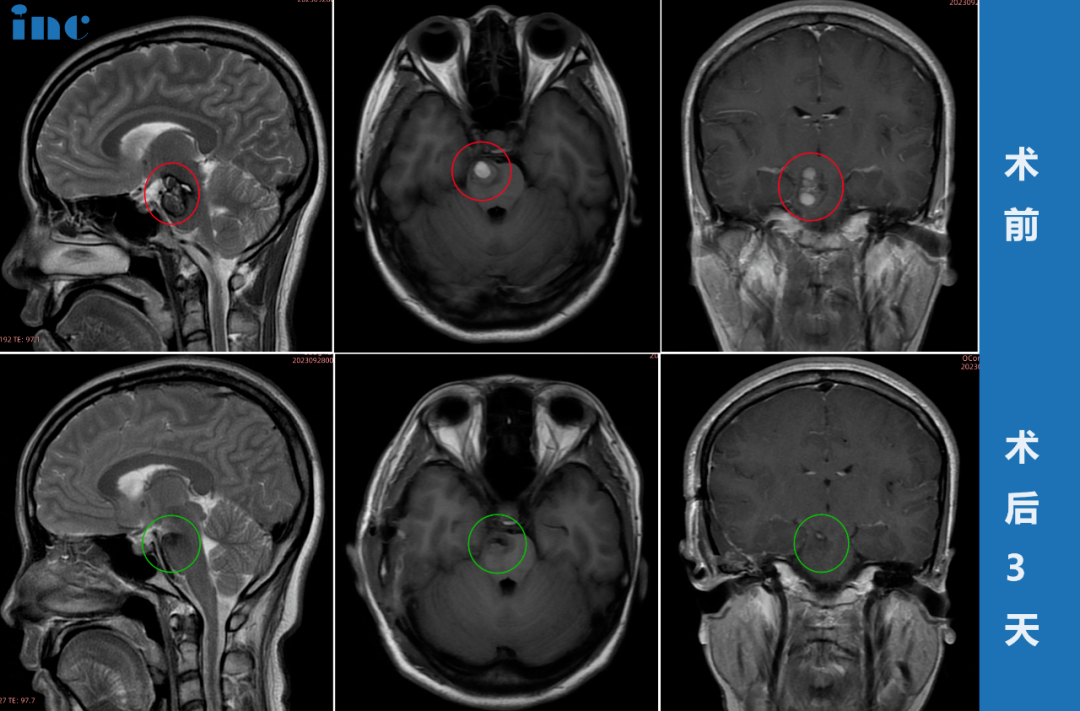

▼30岁女性-丘脑海绵状血管瘤

▼80岁女性-颅咽管瘤

▼11岁男孩-四脑室肿瘤